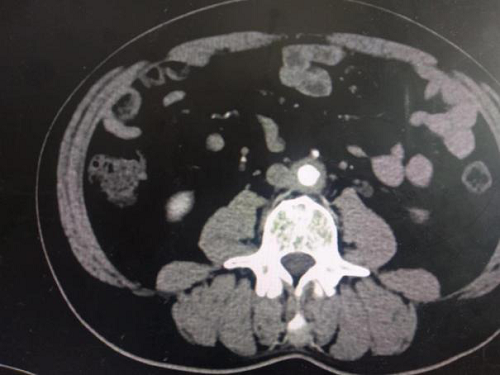

辅助检查:完善泌尿系CTU示腹主动脉下段、双侧髂总动脉周围见软组织影环绕,可见延迟强化,于左侧髂总动脉水平病变与左输尿管分界不清,相应水平左输尿管狭窄,以上输尿管,肾盂、肾盏扩张积水,腹腔、腹膜后未见明显肿大淋巴结。(如下图1-4)

(图1-4泌尿系CTU示考虑腹膜后纤维化累及左输尿管致尿路梗阻)